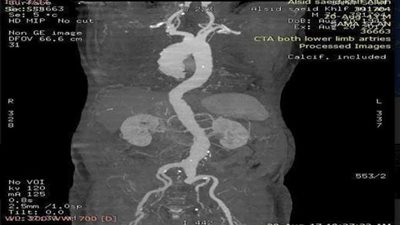

إجراء عملية تمدد بالشريان الأورطي دون جراحة بالتأمين الصحي بالقليوبية